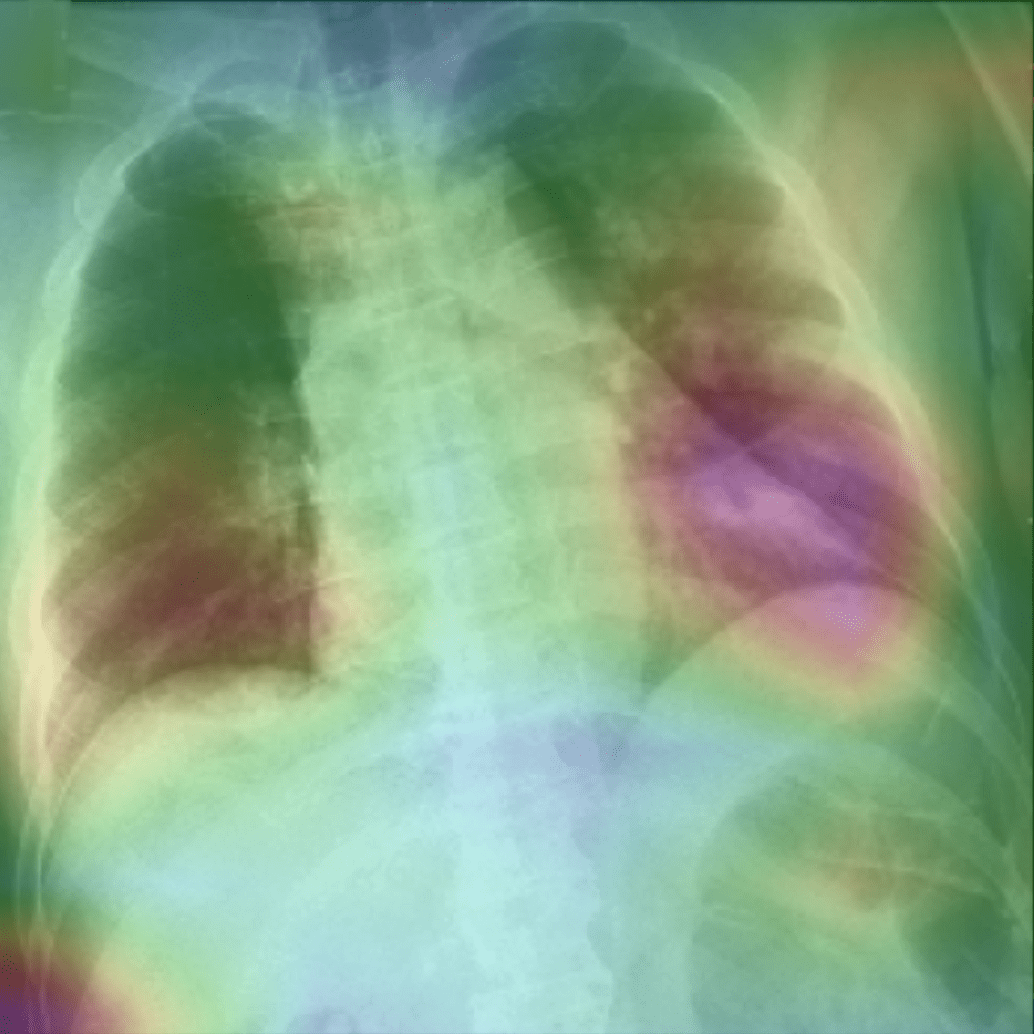

While text removal methods can prevent overfitting, we can simply force the model to look into the lungs in order to address both problems in one effort. To accomplish this task, a U-Net based segmentation illustrated in Fig. 4 is applied to the input images before enhancements. Visualization results for COVID-CXNet with the ROI-segmentation block are shown in Fig. 18.

Refer to caption

Figure 18: Grad-CAM visualization of the proposed model, trained with lung-segmented CXRs, over sample cases.

A figure with more Grad-CAMs is attached in Appendix B. From Fig. 18, it can be observed that COVID-CXNet with ROI-segmentation has delivered superior performance regarding the localization of pneumonia features. Worthwhile to mention that image augmentation is expanded by adding zoom-in, zoom-out, and brightness adjustment. Label smoothing is also applied to the loss function.

The proposed method has shown a negligible drop in metric scores; accuracy is decreased by 0.42%, and f-score is declined by 0.02. This decrease is a result of training with a larger dataset and accurately segmented ROIs, which means it has become more robust against unseen samples. There is a trade-off between catching good features and higher metric scores; while better features result in a more generalized model, high metric scores may indicate overfitting.